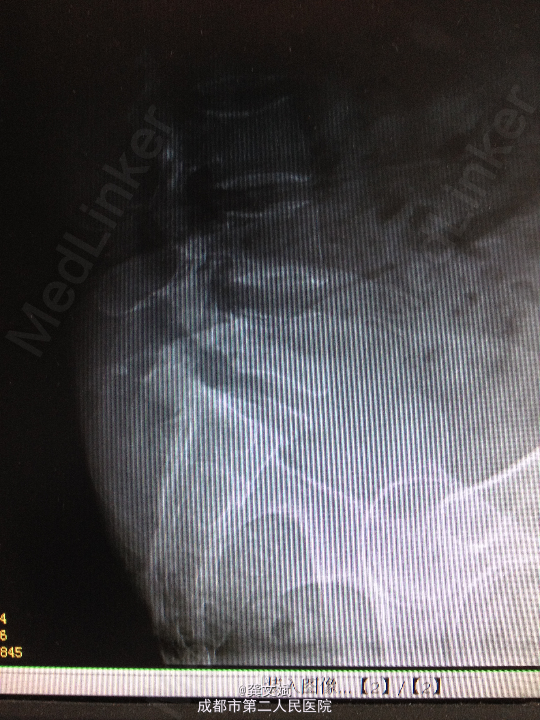

患者女,67岁,因“腰腿痛2月”入院。患者于入院前2月,无明显诱因出现腰腿痛,弯腰时腰痛加剧,无下肢麻木症状及乏力,无大小便障碍。于当地医院行X线提示要5滑脱。

腰5椎体棘突台阶感,腰5水平棘突、椎旁压痛、叩击痛。双下肢肌力、肌张力正常,双侧直腿抬高试验(+)。

诊断:腰5椎体滑脱(I°)、腰5椎体双侧峡部裂 处理:腰5椎间盘摘除、滑脱复位、椎间植骨融合内固定